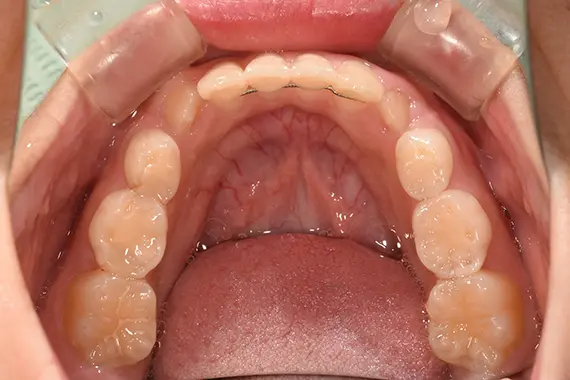

矯正後:下側

| 治療名 | ムーシールド使用の一期治療(就学前の一期治療) |

| 治療回数・期間 | 約3年(ムーシールド2年・一期治療1年) |

「受け口」への対処を早期の内に行うと、「上あごの成長阻害」という重大な弊害を回避することが出来ます。 「受け口」の治療は長期間になりますし、経過観察もしっかりと診てゆく必要がある治療です。 |